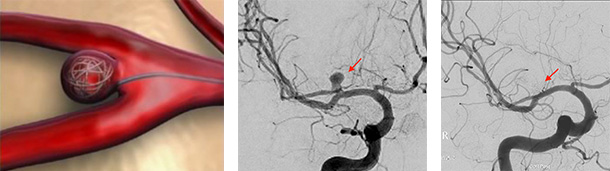

2)血管内治療: 動脈瘤コイル塞栓術、フローダイバーター

2)血管内治療(コイル塞栓術、フローダイバーター):足の付根の血管からカテーテルを挿入し、そこから動脈瘤のある脳血管までカテーテルを進めていきます。腕の血管からカテーテルを挿入することもあります。動脈瘤の内部に約0.3mm~0.5mm程度の太さのコイル(プラチナ製)を充填していくことで、動脈瘤内へ行く血流を遮断し、破裂を防ぐ方法です。動脈瘤の大きさや形状によっては、フローダイバーターというステントを動脈瘤ができている脳血管に留置することで治療が可能な場合があります。患者さんへの侵襲が少ない治療であり、近年道具の発達に伴って進歩している治療法になります。